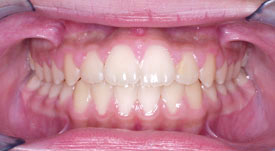

Crossbite

Crowding Front

Crowding Lower

Crowding Upper

Midlines

Narrow Upper Arch

Openbite

Overbite Front

Overbite Side

Protrusion

Spacing

Underbite